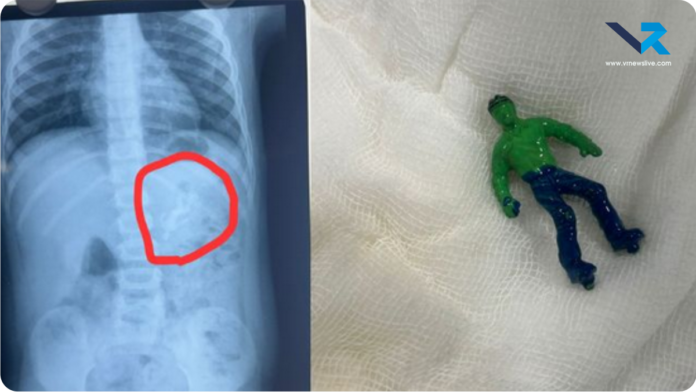

घटना का विवरण अहमदाबाद के सिविल हॉस्पिटल में हाल ही में एक दिल दहला देने वाला मामला सामने आया। एक डेढ़ साल का बच्चा घर में खेल रहा था, तभी उसने अचानक ‘हल्क’ (Hulk) नाम का एक छोटा प्लास्टिक का खिलौना निगल लिया। खिलौना बच्चे के भोजन की नली (Esophagus) में फंस गया, जिससे उसे सांस लेने में तकलीफ होने लगी और वह तड़पने लगा।

परिजन तुरंत उसे सिविल हॉस्पिटल ले गए, जहाँ डॉक्टरों की एक विशेषज्ञ टीम ने स्थिति की गंभीरता को देखते हुए फौरन सर्जरी का फैसला लिया। करीब 45 मिनट तक चली इस जटिल एंडोस्कोपिक सर्जरी के बाद डॉक्टरों ने खिलौने को सुरक्षित बाहर निकाल लिया। डॉक्टरों का कहना है कि अगर थोड़ी भी देरी होती, तो खिलौना बच्चे की श्वसन नली को पूरी तरह ब्लॉक कर सकता था, जो जानलेवा साबित होता। फिलहाल बच्चा पूरी तरह स्वस्थ है और उसे अस्पताल से छुट्टी दे दी गई है।